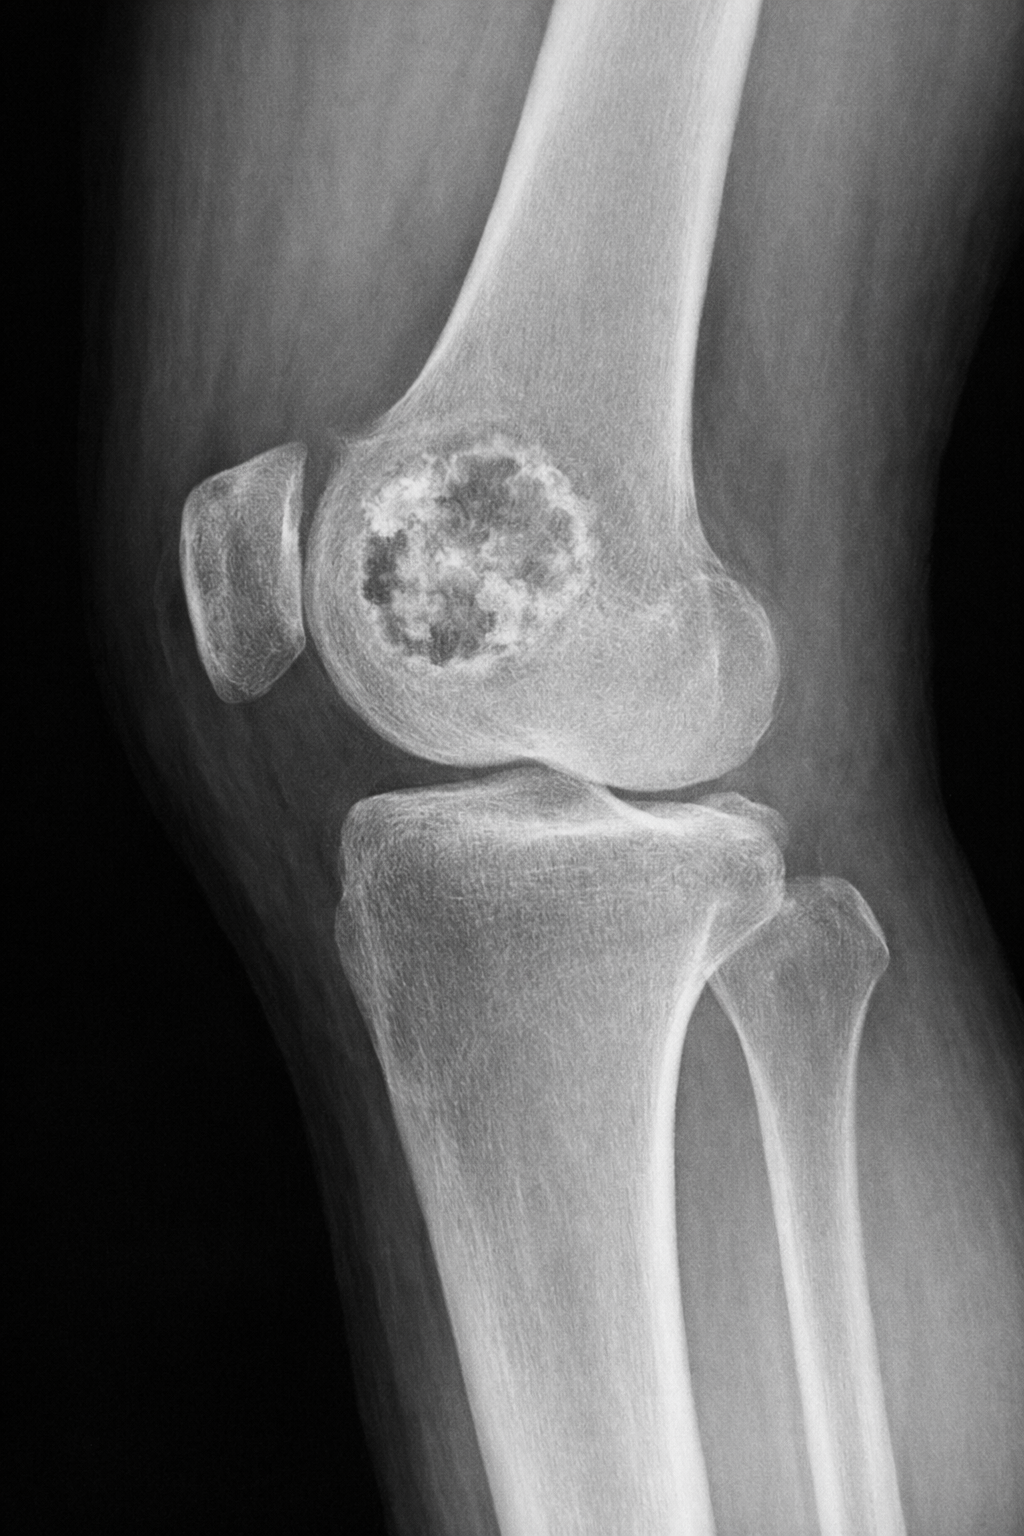

Los hallazgos de imagen en el condroblastoma son característicos pero no patognomónicos. La radiografía simple muestra una lesión lítica epifisaria, a menudo excéntrica, con bordes bien definidos y ocasionalmente calcificaciones puntiformes en su interior. Puede observarse una reacción perióstica moderada y expansión cortical en algunos casos.

📷 Radiografía

Lesión lítica epifisaria, excéntrica, con posibles calcificaciones puntiformes. La TC es útil para identificar calcificaciones sutiles y evaluar la integridad cortical, ayudando en la planificación quirúrgica.